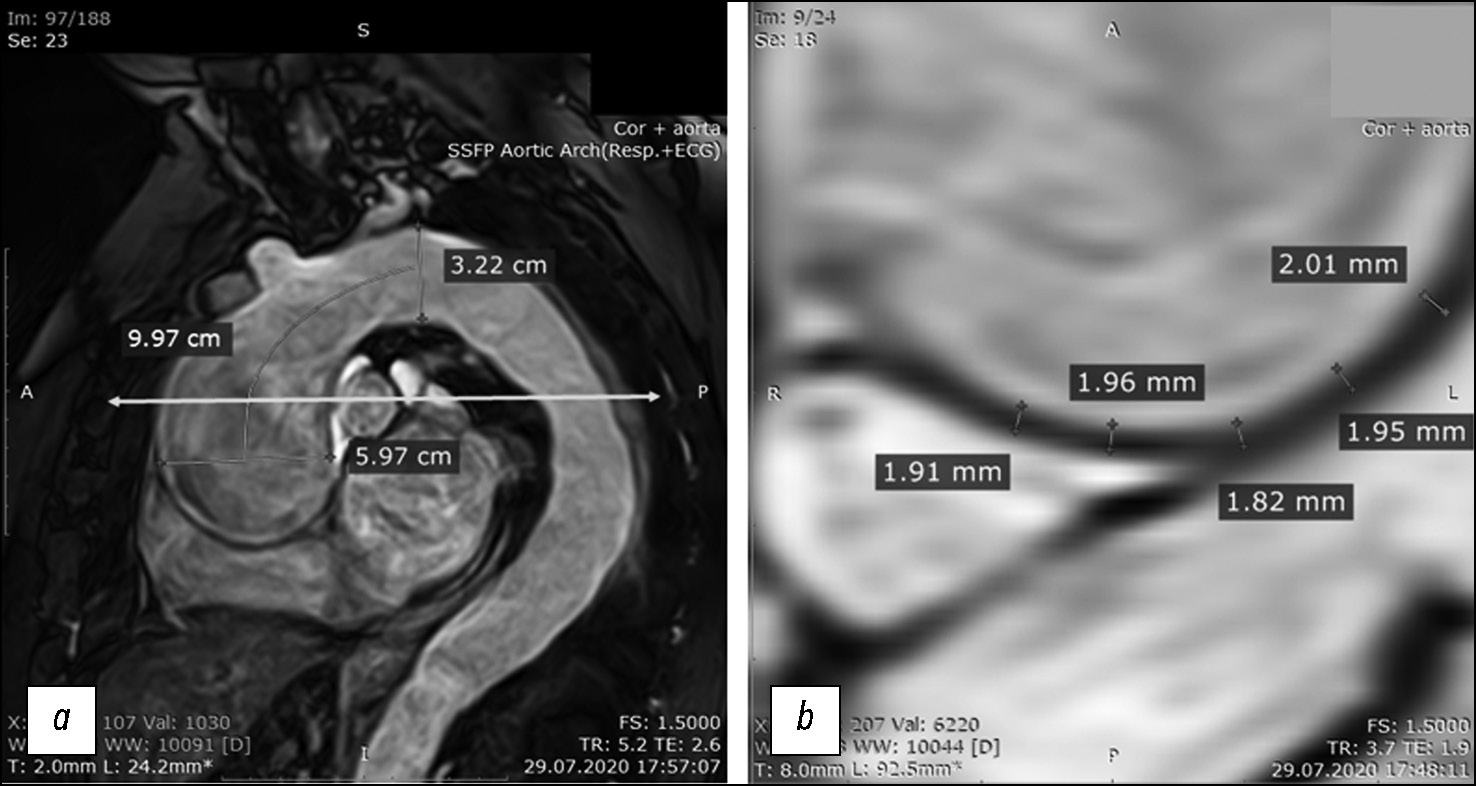

Fig. 2. Magnetic resonance imaging with ECG gating in patient B-k: (a) magnetic resonance angiography of the thoracic aorta. The lumen at the supravalvular and aortic arch levels and the distances between them, which are used to calculate the ascending aorta volume during systole and diastole and the systolic expansion volume, are shown. The turquoise horizontal line with arrows at the ends represents the tomographic slice level; (b) transverse tomographic slice of the ascending aorta in the wall area, with thickness measurements for the subsequent calculations of Young’s modulus parameters. The measurements are marked by thin green lines, with respective values.

Following cardiac MRI, the patient underwent MRI of the ascending aorta with ECG gating, at the level of crossover with the pulmonary artery bifurcation level, in axial plane, in the cine mode (24 cine frames per cardiac cycle), with the assessment of changes in the aortic wall thickness during a cardiac cycle (Fig. 2b) and diameter and cross-sectional area of the lumen at the study level (marked with an arrow in Fig. 2a). The cardiac MRI findings were processed using a standard method; the left ventricular end-diastolic volume, left ventricular end-systolic volume, and left ventricular ejection fraction were calculated. Moreover, biomechanical parameters of aortic distensibility were obtained based on non-contrast-enhanced cine mode MRI findings.

h = aortic wall thickness during diastole (Fig. 2b),